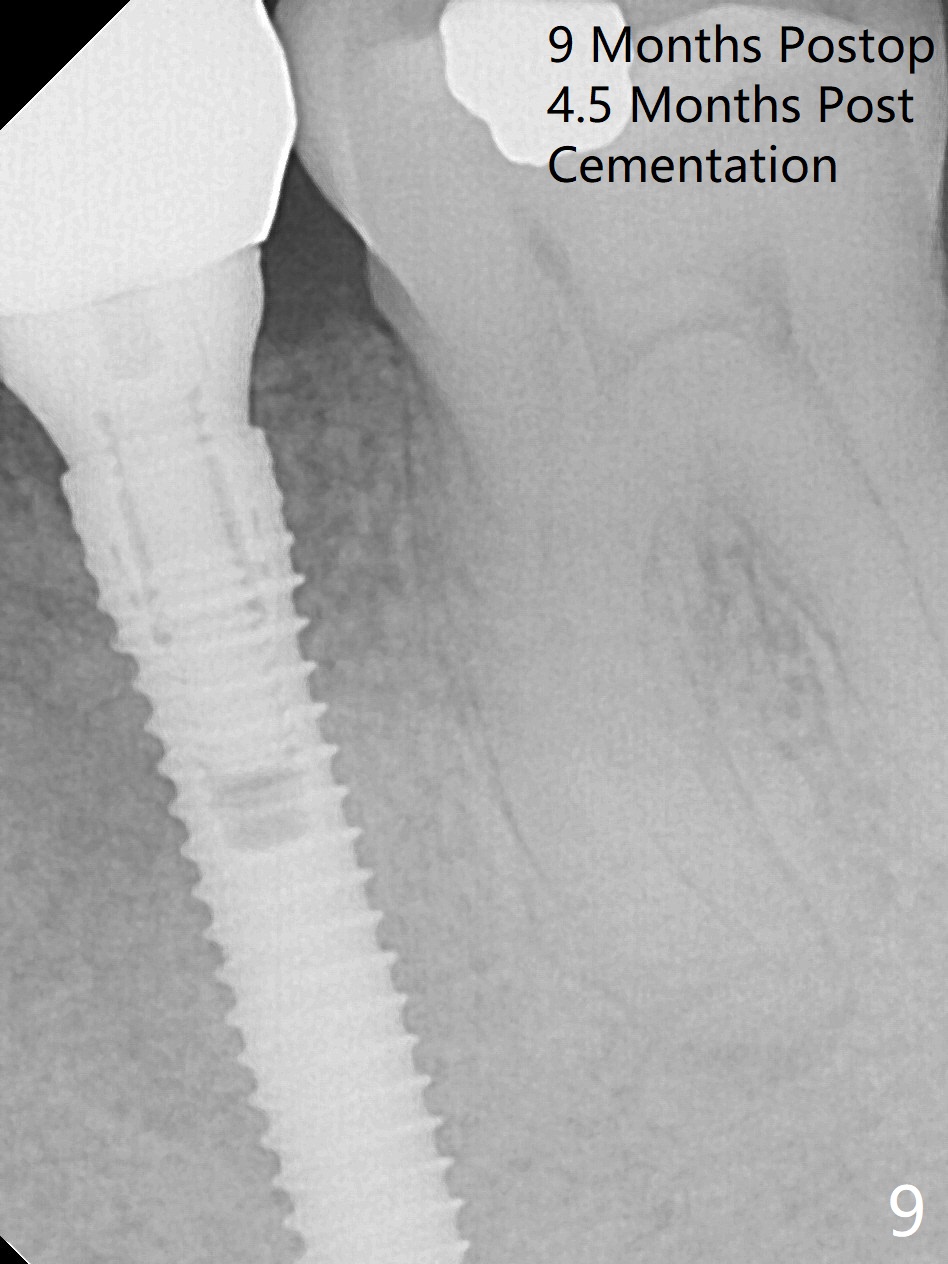

Extraction of the lower left 2nd premolar with vertical fracture (Fig.1,2 >) is easy because of peri-radicular radiolucency.  The apical end of the osteotomy is not shown with a 2 mm pilot drill (Fig.3) or a 3.8x18 mm implant (Fig.4) in place.  It appears that the implant is not placed deep enough.  Following 3-4 more turns of the implant and placement of a 5.5x4(3) mm abutment (Fig.5 A), allograft is placed (*).  A postop panoramic X-ray is taken (Fig.6); the osteotomy could have been deepened to reduce the possibility of periimplantitis.  Retrospectively, the panoramic X-ray should be taken after use of the pilot drill. The bone around the implant appears to have regenerated 4 months postop (Fig.7,8).  Bone density appears to continue increasing 9 months postop (i.e., 4.5 months post cementation, Fig.9).  Bone loss is minimal 2 years post cementation (Fig.10).